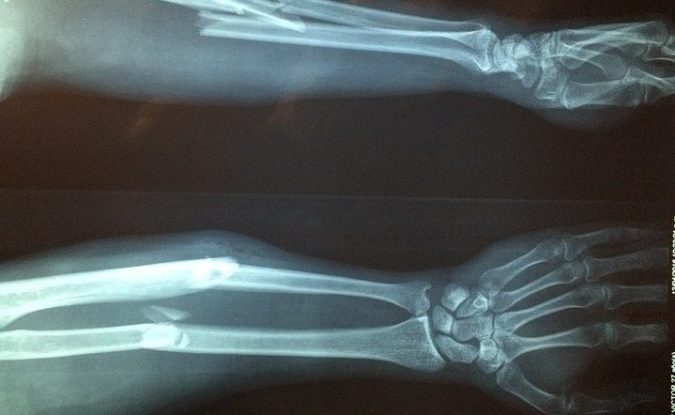

View Broken Leg Recovery Time Elderly US. There are four bones in the leg that may break due to injury for instance, an elderly person with a hip fracture may have difficulty regaining strength and kevin ware, guard for the louisville cardinals, had jumped to block a shot thousands of times in practice. Information about broken leg bones.

However, the length of recovery time depends on where you break the femur collarbone breaks are the most common fracture in cycling, with neck and vertebrae cracks not unusual either. Most people get the green light from their doctor to slowly start putting weight on their leg around six weeks after breaking their ankle, although this may be less or more depending on your injury. Common questions and answers about broken leg recovery time cast. It's also referred to as a leg fracture.